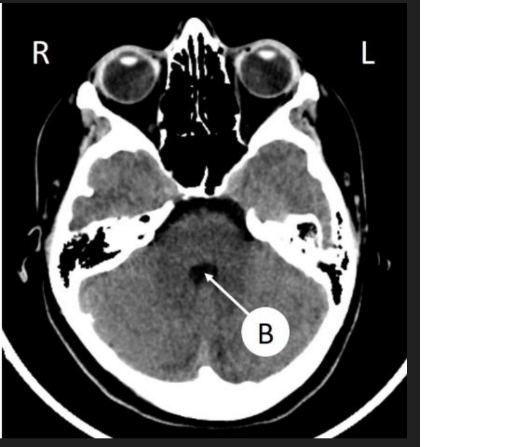

medulla oblongata

mesencephalon

pons

ventriculus IV

Vermis cerebelli

hemisphaerium dex. cerebelli

Aquaeductus mesencephali